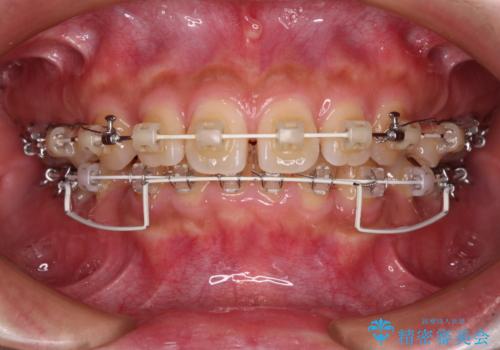

- 矯正装置

- 審美装置

- 前歯の突出感を気にして来院された患者様です。

咬合力が非常に強く、咬合力で前歯が前方に押し広げられており、上下唇に閉じにくさが認められました。

上下左右の第一小臼歯4本を抜歯し、ワイヤー装置にて矯正治療を行うこととしました。

強い咬合力により前歯の隙間がなかなか閉じられず、治療期間は長いものとなりましたが、横顔の印象が大きく変わるほど口元の印象を改善することができました。